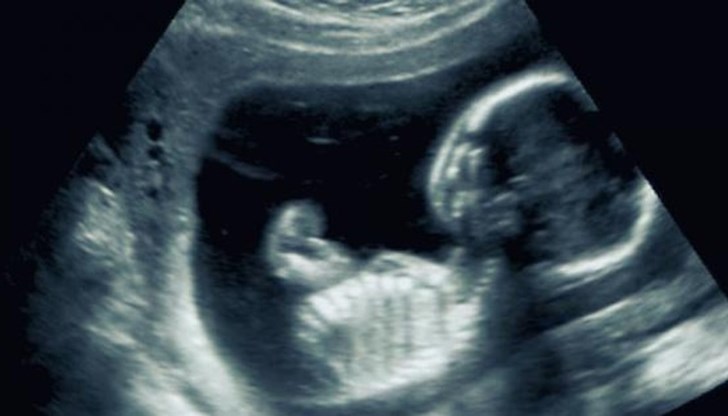

Бременността минава гладко, докато по време на рутинен ултразвуков преглед не се оказва, че жената носи в утробата си още един плод. Лекарите смятат, че става дума за разделяне на ембриона - рядко, но все пак напълно възможно явление, и очакват еднояйчни близнаци. Никой не предполага, че може да е настъпил много по-редкия феномен, известен като „суперфетация“.

Това явление е възможно единствено, ако жената продължава да има овулация след забременяването и може да зачене второ дете, което се развива в утробата едновременно с първото. Макар и да е изключително рядко при хората (в медицинската литература са известни около 10 случая) явлението е по-често срещано в животинското царство, сред бозайници и двуутробни.

Алън ражда предполагаемите близнаци с Цезарово сечение, след което се установява, че децата не са еднояйчни близнаци е едното е по-малко от другото. Седмици по-късно ДНК тестовете потвърждават, че едното от бебетата носи гените на китайската двойка, а другото – Алън и Джаспър.